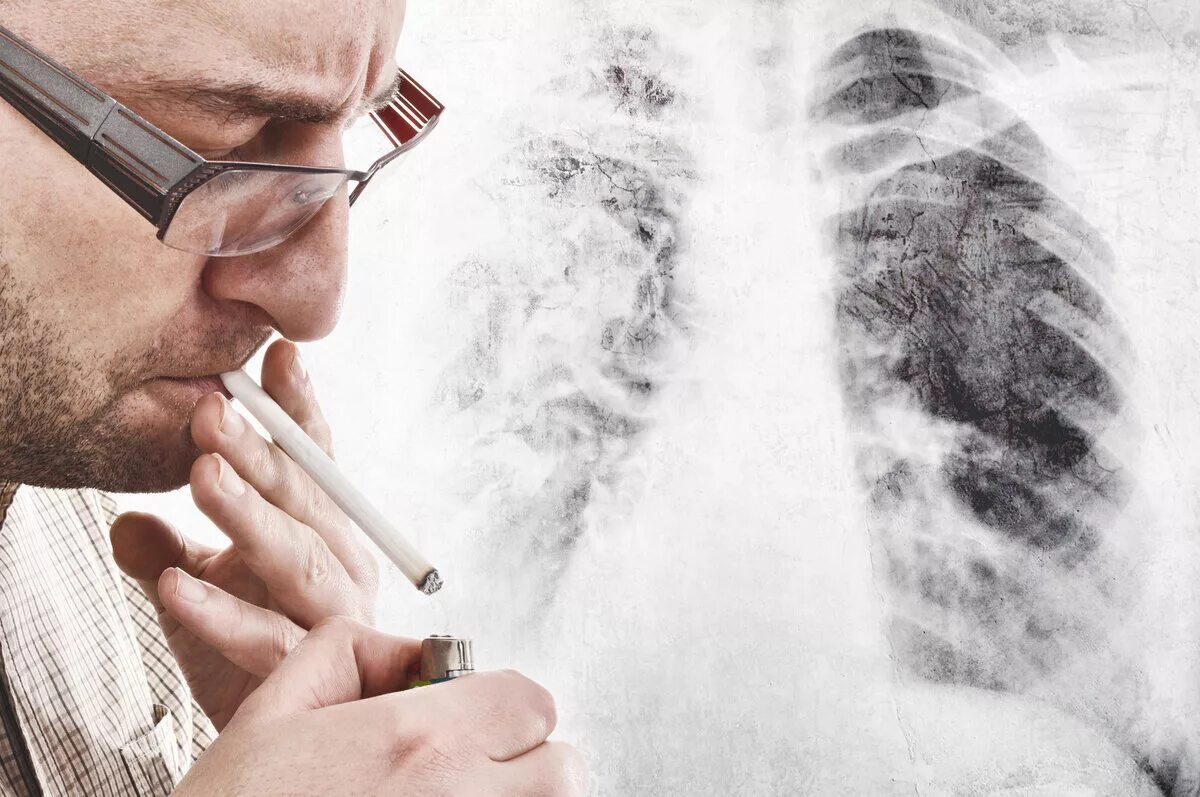

Снимок курильщика